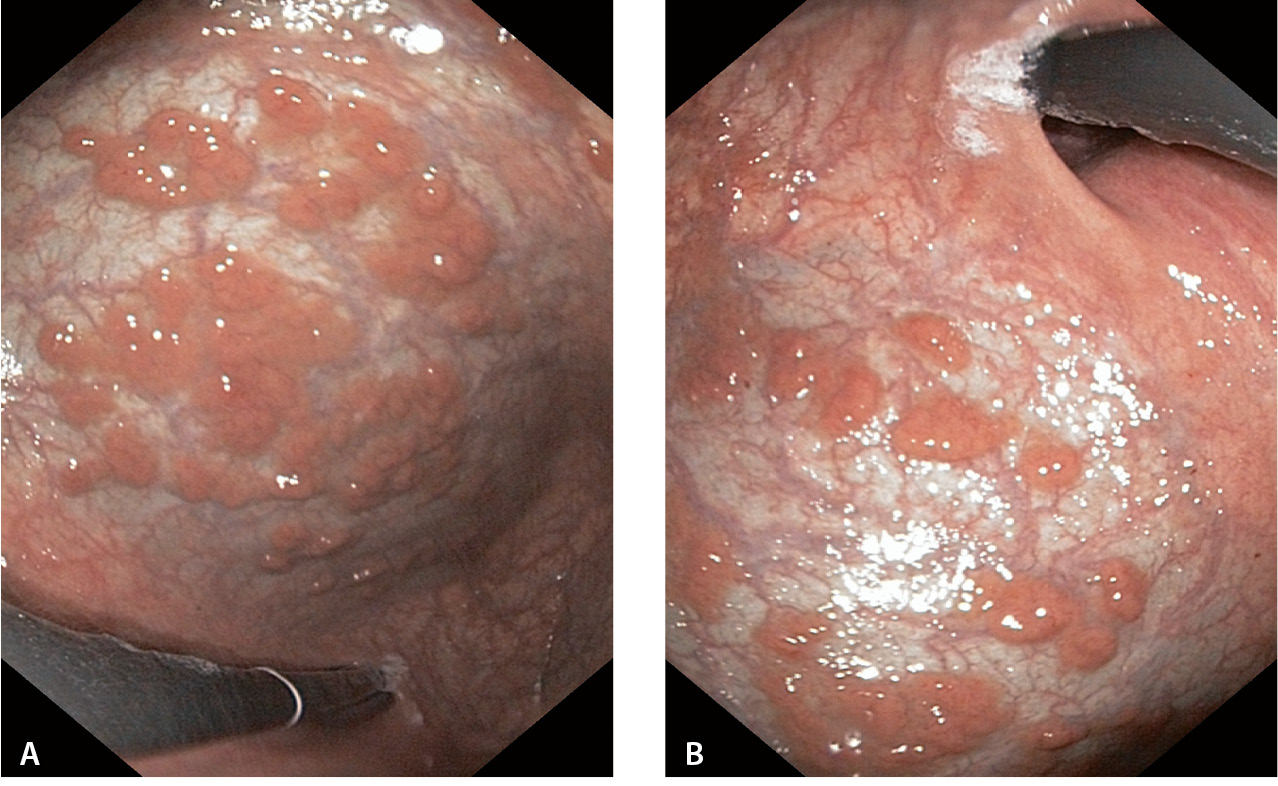

Длительное применение ИПП вызывает такие гистопатологические изменения слизистой оболочки желудка, как гиперплазия париетальных клеток с выпячиванием их в просвет железы, кистозная дилатация фундальных желез и гиперплазия фовеолярного эпителия (рис. 3). При эндоскопическом исследовании эти изменения выявляются в виде полипов фундальных желез (рис. 4), гиперпластических полипов, множественных приподнятых поражений, булыжноподобной слизистой оболочки [11]. Клиницисты не всегда уделяют должное внимание этой проблеме. Вместе с тем установить клиническую значимость данных поражений можно только на основании результатов долгосрочных проспективных исследований [12].

Рис. 4. Полипы фундальных желез: А – на фоне длительного (2,5 года) приема ингибиторов протонной помпы; Б – сохраняющиеся через 3 года после отмены приема ингибиторов протонной помпы (из личного архива Н.М. Хомерики)